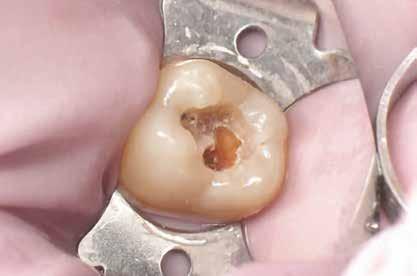

Egy 31 éves férfi páciens jelentkezett a jobb felső első molárisából kiinduló, reverzíbilis pulpitisre utaló tünetekkel. A klinikai vizsgálat során meglévő okkluzo-palatinális ezüsta-

malgám restauráció volt észlelhető, valamint szekunder caries mesiálian, a marginális gerinc kavitációjával együtt (10. ábra). A mesio-bukkális csücsök csúcsán kopási fazetta volt látható; a fog egyébként klinikailag és radiológiailag épnek bizonyult. A tájékoztatáson alapuló beleegyezést követően a kezelési terv II. osztályú, háromfelszínű direkt kompozit restauráció volt.

A szerző helyi érzéstelenítés után a fogat latexmentes kofferdámmal izolálta; a gumit befordította, és közben fogselyem segítségével interproximálisan visszahúzta (11. ábra)

Nagyítás alatt (operációs mikroszkóp) a régi restaurációt körte alakú gyémántfúróval távolította el, 1,5-es sebességfokozatú elektromos kézidarabbal kb. 45 000/ perc fordulatszámon vízhűtés mellett, így a mesiális oldalon feltárta a szuvasodást. A szerző az elektromos kézidarabot részesíti előnyben a nagy nyomaték és a kisebb, alacsonyabb sebességnél előforduló torpanási hajlam miatt. A szomszédos premoláris fogat ék (Triodent) segítségével védte az iatrogén sérülésektől (12. ábra). A szomszédos fog iatrogén sérülése jól dokumentált komplikációja a II. osztályú üreg dobozpreparációjának [18].

A cariest lépésről-lépésre távolította el, caries detektáló festék és a Peripheral-Seal koncepció [15] alkalmazásával, amely lehetővé teszi a magas kötőerejű, cariesmentes zománc- és dentinzóna kialakítását a kavitás peremén, miközben a mélyebben lévő, caries által érintett dentin megmarad remineralizáció céljából [16]. A preparáció szélét alumínium-oxid abrázióval kezelte a biofilm és az aprizmatikus zománc eltávolításának céljából, ezzel javítva a kötőerőt [17]; majd karbidfúrókkal elsimította, hogy eltávolítsa a mikroszkopikus szinten törött zománcprizmákat, így csökkentve a „Enamel Peel”-ből eredő fehér vonalak kialakulásának kockázatát (13. ábra) [18].